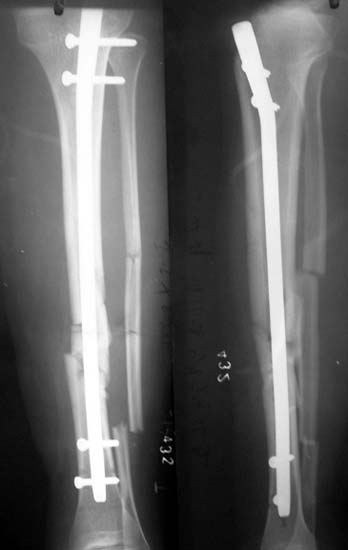

胫腓骨粉碎骨折 采用闭合穿钉法,带锁髓内钉内固定